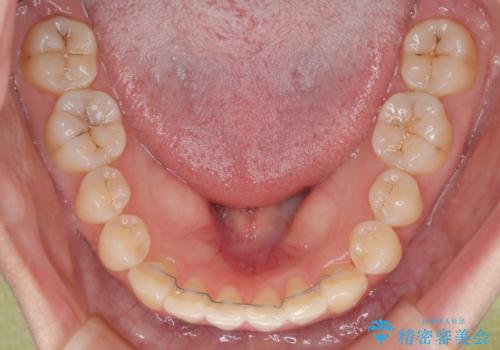

診察の結果、上下の前歯部に**叢生(そうせい/歯のガタガタ・重なり)**が認められました。

特に上の前歯にはねじれや重なりがあり、審美的にも清掃性にも影響している状態でした。

前歯のデコボコがなくなり、見た目の印象が大きく変わっただけでなく、歯磨きがしやすくなり、むし歯や歯周病のリスクが大きく減少しました。